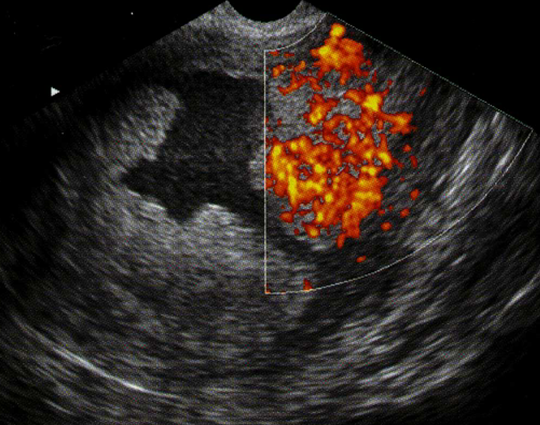

- Siêu âm: giúp đánh giá độ dày và cấu trúc của niêm mạc tử cung.